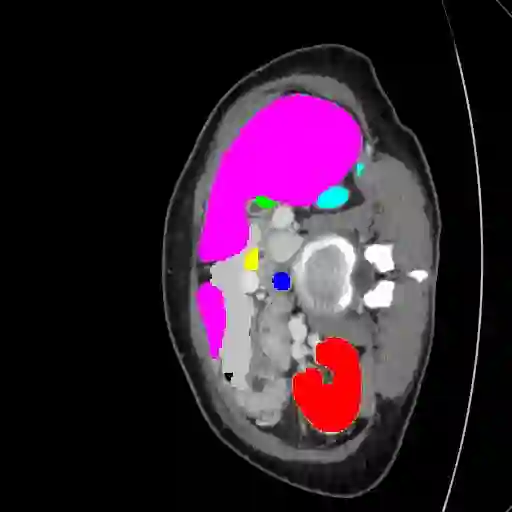

Transformers have made remarkable progress towards modeling long-range dependencies within the medical image analysis domain. However, current transformer-based models suffer from several disadvantages: (1) existing methods fail to capture the important features of the images due to the naive tokenization scheme; (2) the models suffer from information loss because they only consider single-scale feature representations; and (3) the segmentation label maps generated by the models are not accurate enough without considering rich semantic contexts and anatomical textures. In this work, we present CASTformer, a novel type of generative adversarial transformers, for 2D medical image segmentation. First, we take advantage of the pyramid structure to construct multi-scale representations and handle multi-scale variations. We then design a novel class-aware transformer module to better learn the discriminative regions of objects with semantic structures. Lastly, we utilize an adversarial training strategy that boosts segmentation accuracy and correspondingly allows a transformer-based discriminator to capture high-level semantically correlated contents and low-level anatomical features. Our experiments demonstrate that CASTformer dramatically outperforms previous state-of-the-art transformer-based approaches on three benchmarks, obtaining 2.54%-5.88% absolute improvements in Dice over previous models. Further qualitative experiments provide a more detailed picture of the model's inner workings, shed light on the challenges in improved transparency, and demonstrate that transfer learning can greatly improve performance and reduce the size of medical image datasets in training, making CASTformer a strong starting point for downstream medical image analysis tasks.